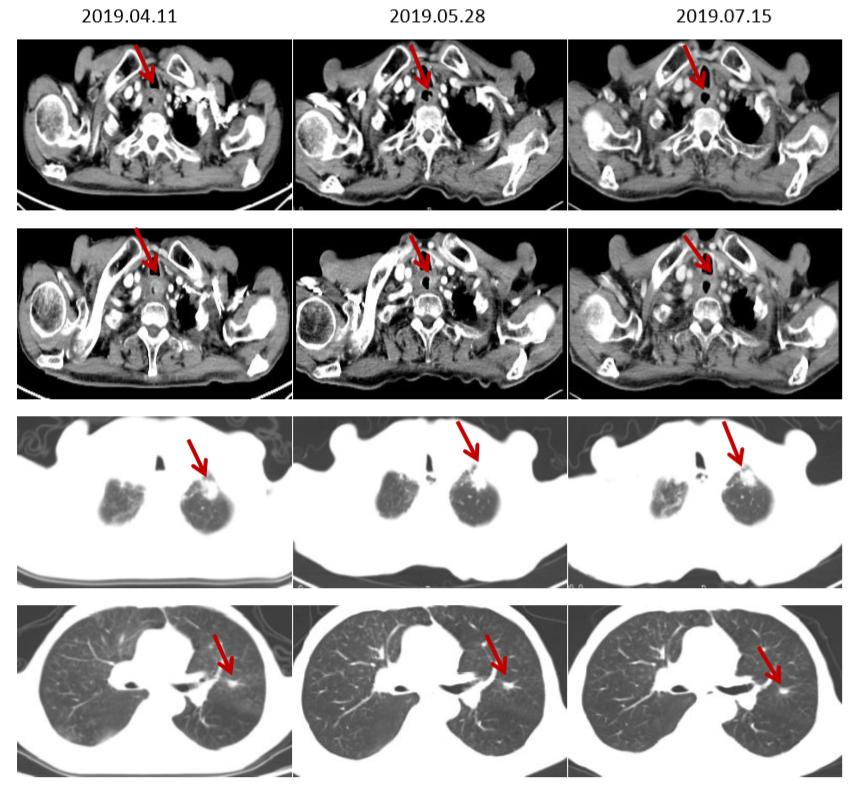

于2019-04-18 2019-05-08、2019-05-30、2019-06-26、2019-07-17、2019-08-09给予“伊立替康+安罗替尼”方案治疗6周期。

CT(食管增厚较前明显改善,肺转移灶较前缩小)

MRI(颅内转移灶持续缩小)